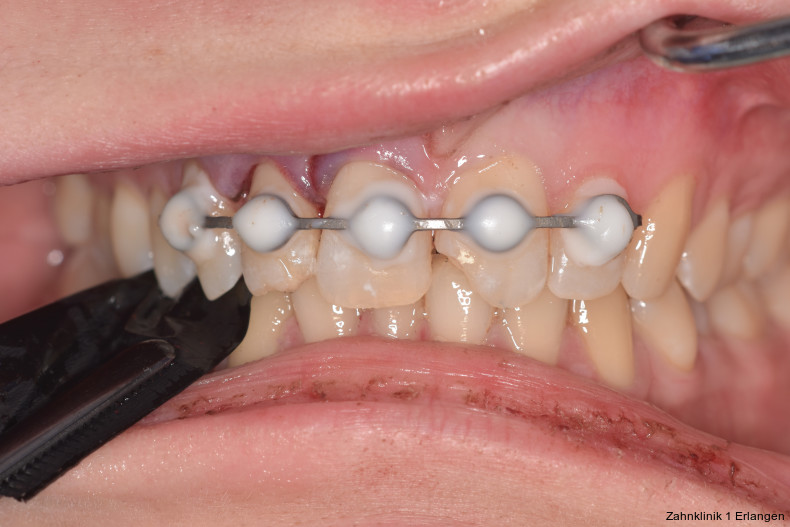

Foto: Zahnklinik 1 Erlangen

Zu den wesentlichen diagnostischen Verfahren, die zur Erfassung des Pulpastatus herangezogen werden, gehören neben der Inspektion und der röntgenologischen Bildgebung die Sensibilitätsprüfung sowie der Perkussionstest. Der Inspektion kommt insbesondere bei der Erstbehandlung eine wesentliche Rolle zu. Hierbei wird abgeklärt, ob es sich bei Zahnfrakturen um eine schmelzbegrenzte Verletzung handelt, ob das Dentin mitbetroffen und ob zusätzlich die Pulpa exponiert ist. Bei Dislokationsverletzungen wird das Ausmaß der Positionsveränderung erfasst und ob zusätzliche Gewebe wie Knochenstrukturen oder umliegende Weichgewebe betroffen sind. Auch können Farbveränderungen des Zahnes erfasst werden. Die Röntgendiagnostik zum Zeitpunkt des Unfalles gibt Aufschluss über die Größe des Pulpenkavums und das Lumen des Wurzelkanals, den Stand des Wurzelwachstums und die periapikalen Verhältnisse. Des Weiteren finden sich möglicherweise Hinweise auf eine Wurzelfraktur.

Versorgung von Zahnfrakturen mit Pulpabeteiligung

Unkomplizierte Kronenfrakturen mit Verlauf im Dentin sind als Wundfläche einzuschätzen, bei der es bei anhaltender Exposition zum Mundhöhlenmilieu zur Infektion der Pulpa über freiliegende Dentintubuli kommen kann. Somit ist ein wesentlicher Grundsatz der Erstversorgung, die Dentinwunde abzudecken,3, 8 vor allem bei jungen Patienten mit großlumigen Dentintubuli. Die Abdeckung kann im Zuge der Notfallbehandlung mit Glasionomerzement erfolgen oder mittels fließfähigem Komposit unter Verwendung eines Dentinadhäsivs. Hilfreich im Hinblick auf die spätere Wiederentfernung ist dabei die Verwendung eines falschfarbenen oder opaken Materials, um die provisorische Abdeckung bei der definitiven Versorgung gezielt wieder entfernen zu können. Bei pulpanahen Verletzungen empfiehlt sich die Abdeckung mit einem biokompatiblen Material wie hydraulischem Kalziumsilikatzement oder Kalziumhydroxid im Sinne einer indirekten Überkappung.3 Betroffene Zähne können durch Wiederbefestigung des Zahnfragmentes9 oder mit Komposit restauriert werden, dies kann jedoch auch erst bei der Weiterbehandlung erfolgen.

Bei Pulpaexposition ist die oberste Prämisse der Erhalt der Vitalität des Zahnes. Vor allem bei jungen Patienten und bei nicht abgeschlossenem Wurzelwachstum, aber auch bei erwachsenen Patienten ist die Vitalerhaltung die Methode der Wahl. Dabei spielen die Dauer und die Größe der Exposition keine wesentliche Rolle.10 Die oberste Gewebeschicht sollte zunächst im Sinne einer Mikropulpotomie angefrischt werden, was mit einem Diamantschleifer unter Wasserkühlung durchgeführt werden kann. Nach Blutstillung, zu der Natriumhypochlorit tropfenweise appliziert werden kann, wird das Sistieren der Blutung kontrolliert. Ist dies verifiziert, wird ein biokompatibles Material in direktem Kontakt mit dem Gewebe aufgebracht und der Zahn anschließend adhäsiv verschlossen.10 Dauert die Blutung an, beispielsweise weil der Unfall bereits mehr als 24 Stunden zurückliegt, kann tiefer pulpotomiert werden. Da eine traumatisch geschädigte Pulpa in der Regel vor dem Unfall gesund war, ist die Heilungskapazität meist sehr gut.11 Auch bei bestehender Exposition zur Mundhöhle hin über einen Zeitraum von Tagen kann die Pulpotomie noch hohe Erfolgsraten erzielen.